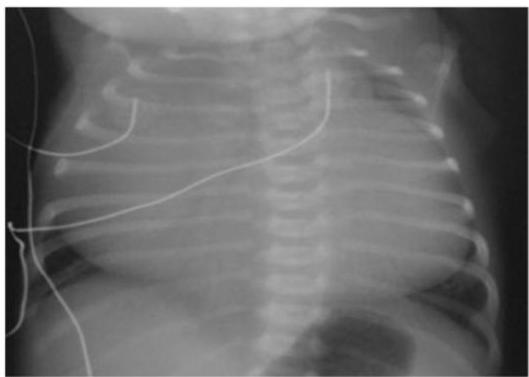

Preterm Infant with Respiratory Distress

- Preterm 29 weeks gestation C/S delivery showed severe respiratory distress soon after birth - RDS

- Air bronchograms

-

There is a homogeneous opacification of both lungs with white-out lungs - (1 .field (grounds glass appearance) and air bronchogram bilaterally

.The diagnosis is Acute Respiratory Distress Syndrome (ARDS) - (2

- .I- Massive blood transfusions Preterm 29-weeks gestation C/S delivery showed severe respiratory distress soon after birth. This chest x-ray was taken at the age of 6 hours.

- Q1: Write 2 abnormalities in the X-Ray?

- Q2: What is the likely diagnosis?

- Q3: Write 2 management steps.

Answers:

- Q1: Ground glass appearance, wide intercostal space.

- Q3: Mechanical ventilation, give Surfactant for lungs maturation.

What are the possible diagnoses? Congenital pneumonia or respiratory distress.

Respiratory Distress Syndrome (Premature Neonate)

X-ray? Ground glass appearance of the lungs with air bronchogram.

Diagnosis? Respiratory Distress Syndrome.